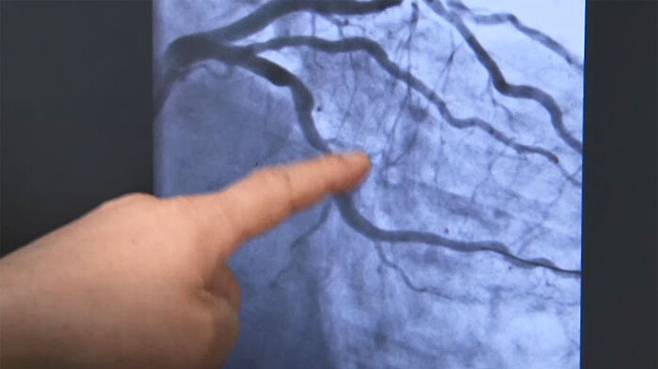

응급실에서 검사해보니 심장혈관 3개 중 2개가 막혀 있었고 스텐트로 막힌 혈관을 뚫는 데 성공했지만, 또 다른 고민이 남았습니다.

[장기육/서울성모병원 심장내과 교수 : 시술 초기에는 (심장 혈관) 살갗이 벗겨졌다. 이렇게 생각되니까 막 핏덩이(혈전)가 생길 우려가 많아서 저희가 이제 약들을 좀 세게 쓰는데….]